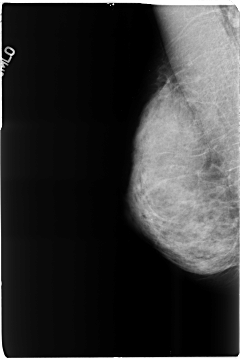

B_3516_1.RIGHT_MLO

RIGHT_CC LINES 4680 PIXELS_PER_LINE 3104 BITS_PER_PIXEL 12 RESOLUTION 50 NON_OVERLAY

RIGHT_MLO LINES 4664 PIXELS_PER_LINE 3112 BITS_PER_PIXEL 12 RESOLUTION 50 NON_OVERLAY